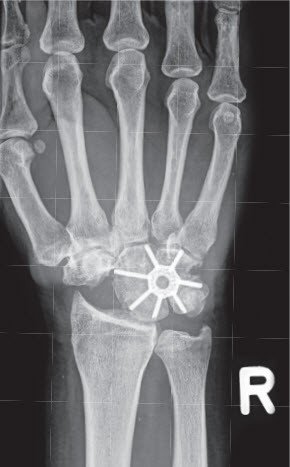

Zu den Hauptspezialitäten gehören der Kunstgelenkersatz an der Hand, komplexe Handgelenkchirurgie und die Behandlung des Morbus Dupuytren, wobei hier auch eine neue konservative Therapie mittels Kollagenase-Infiltration zum Einsatz kommt. Die Patienten der Handchirurgie profitieren von einer umfassenden fachspezifischen Betreuung, die auf langjähriger Erfahrung, kontinuierlicher Lehrtätigkeit und wissenschaftlicher Forschung basiert. Neben Erstbehandlungen werden auch detaillierte Zweitmeinungen und Gutachten angeboten.

Um eine breite Dokumentation und Nachkontrolle neuer Prothesen und Behandlungsmethoden zu gewährleisten, arbeiten wir eng mit der wissenschaftlichen Abteilung zusammen. Dies erlaubt uns, Früh- und Spätkomplikationen zu erfassen und bei Bedarf entsprechende Massnahmen zu ergreifen oder die Wirksamkeit neuer Operations- / Therapiemethoden zu belegen. Hierfür werden neben der klinischen Kontrolle auch international anerkannte Patientenfragebogen, wie zum Beispiel den Michigan Hand Outcomes Questionnaire, abgegeben. Diese werden von den Patienten vor und nach einem Eingriff ausgefüllt und geben einen Überblick über die Beschwerden und Fähigkeiten, bestimmte Tätigkeiten auszuführen. Die Zusammenarbeit mit der Forschungsabteilung ermöglicht uns auch die Entwicklung und die Nachkontrolle eigener Kunstgelenke, wie zum Beispiel der seit 2010 eingesetzten Oberflächenersatzprothese für Fingermittelgelenke (CapFlex®).

- Gelenkersatz an Hand- und Fingergelenken